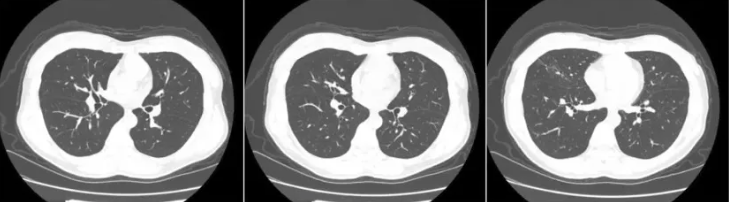

4月前CT: